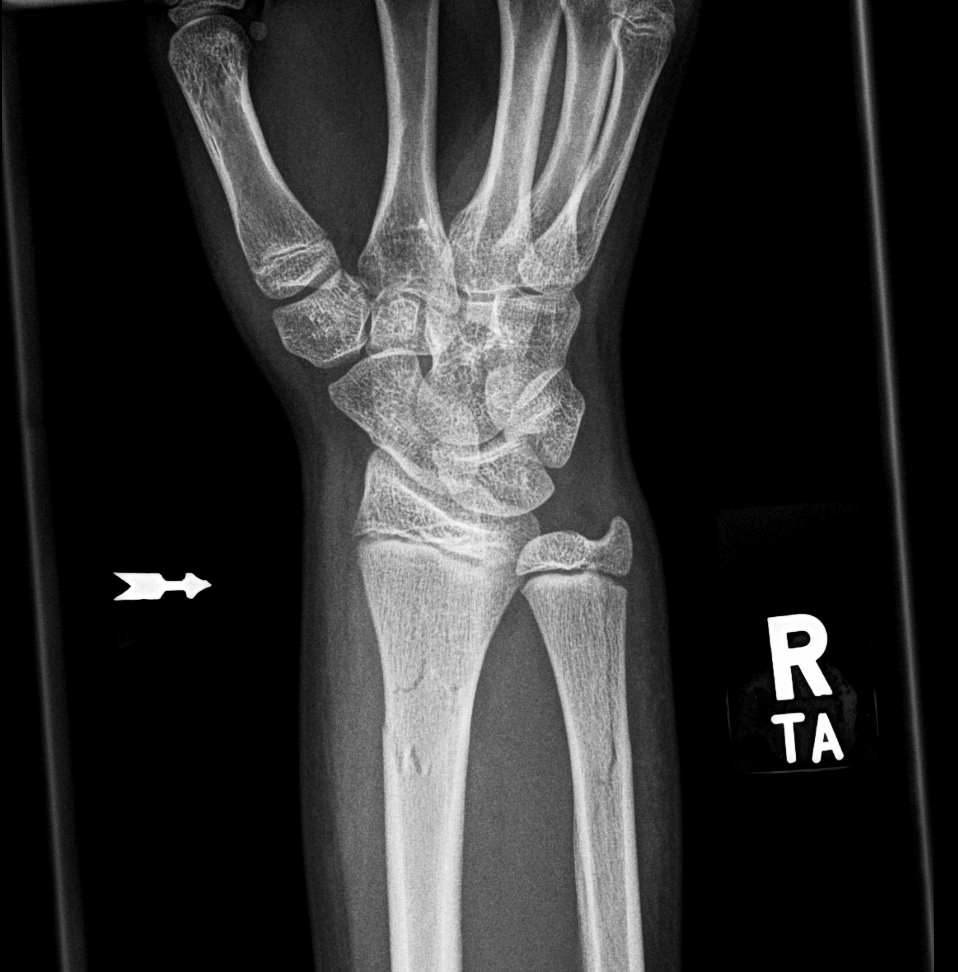

Info Images Findings Impression Reco/Acuity Case Images View Images / Launch Visage Case Notes History 2-month-old presents with decreased right arm movement, increased fussiness, and increased sleepiness for 2 days. Suspected non-accidental trauma. Exam Skeletal survey Prior Study none Dicom View Reference Material

Section 1 Submit Findings CB1550 Findings Skeletal Survey - Technique Check Skull AP/Lat Yes No Cervical and Thoracolumbar spine Yes No Chest X-Ray Yes No Ribs – Left/Right Oblique Yes No Abdominal X-Ray Yes No Pelvis with both hips Yes No Bilateral Humerus, Forearm, Hand Yes No Bilateral Femur, Tibia/fibula, feet Yes No Any additional lateral views of the extremities Yes No The exam is over or under penetrated. Yes No The exam may or may not be limited by overlying structures or soft tissues, body habitus, patient positioning, support devices, or motion. Yes No The area of concern is indicated by the patient, technologist, or care provider. Yes No The area of concern is included on the exam. Yes No Soft Tissues There is soft tissue swelling, indistinctness of fat/muscle planes, gas, or laceration in the area of clinical concern. Yes No There is an effusion, fat pad displacement, or fat fluid level. Yes No There is a radiodense or lucent foreign body. Yes No There are other densities, calcifications, post-surgical changes, or support devices in the soft tissues. Yes No Any support lines/tubes. Yes No Bone There is a break or interruption of the continuity of the cortical or cancellous bone. Yes No There is overriding of the trabeculae with apparent sclerosis. Yes No There is displacement of a fracture fragment. Yes No There is bowing of the bone in addition to the fracture at the apex of the bowed bone concerning for the greenstick. Yes No There is a spiral fracture of the leg concerning for toddler’s fracture. Yes No There is abnormal angulation or bulging of the cortical surface relative to the normal cortex which could be from a buckle or torus fracture. Yes No There is a displaced fragment which may be from avulsion by a tendon, ligament, or joint capsule or from a comminuted or other fracture. Yes No The stress trabeculae or other trabeculae of the cancellous bone are interrupted or otherwise abnormal. Yes No There is subperiosteal or endosteal reaction which could indicate a healing or subacute fracture or other abnormality. Yes No There is hard/soft callus formation. Yes No There is remodeling of the bone. Yes No There is a corner fracture or metaphyseal lesion that could be from nonaccidental trauma. Yes No There are multiple fractures of different ages. Yes No There are vertebral body/spinous process fractures. Yes No There are rib fractures. Location - posterior or lateral. Yes No There is scapular/sternal fracture. Yes No There are fractures of the digits. Yes No There are wormian bones. Yes No There are intrasutural bones. Yes No There is metaphyseal abnormality (lucencies, increased density, erosion) which may be from something other than injury such as stress, metabolic disease (e.g. rickets with loss or distortion of the zone of the provisional calcification), neoplasm (e.g. leukemia), heavy metals, inflammation, or infection. Yes No There are metaphyseal spurs. Yes No There are bony deformities involving multiple bones. Yes No The bones are gracile. Yes No There are non-healing fractures. Yes No There is/are focal or multifocal lytic/lucent, blastic/sclerotic or mixed density lesion(s) or other abnormality. Yes No Overall bone density is increased or decreased with or without thinning or thickening of the cortical or cancellous bone. Yes No Growth plates, ossification centers, apophyses The growth plate(s) is/are abnormal. Yes No There is widening of the physis from a fracture with or without displacement of the epiphysis (Salter-Harris I). Yes No There is a fracture through the physis which then extends into the metaphysis with or without angulation or displacement (S-H II). Yes No There is a fracture through the physis which then extends into the epiphysis and is intra-articular, with or without angulation or displacement (S-H III). Yes No There is a fracture through the metaphysis, physis, and epiphysis which extends into the joint space with or without angulation or displacement (S-H IV). Yes No There is narrowing of the physis from a compression fracture (S-H V). Yes No The apophysis, epicondyle, secondary ossification center, or accessory ossicle is displaced or otherwise abnormal. Yes No The ossification centers are underdeveloped. Yes No Joints and alignment There is an effusion, fat pad displacement, or fat fluid level. Yes No The epiphysis or subchondral bone is fractured, interrupted, flattened, compressed, impacted, displaced, or otherwise abnormal. Yes No There is an intra-articular loose body or chondrocalcinosis. Yes No The joint is widened, narrowed, dislocated, malaligned, or incongruent. Yes No There is pseudoarthrosis. Yes No Other findings There are developmental changes or other anatomic variants or other existing conditions that may or may not be contributing to symptoms which can or should be further evaluated non-emergently or are otherwise incidental. Yes No The remainder of the exam is abnormal for age. Yes No The lungs show focal airspace opacity. Yes No There is pneumothorax. Yes No There is organomegaly. Yes No There is intra-abdominal calcification. Yes No There is displacement of the bowel loops. Yes No There is free intraperitoneal air. Yes No The bowel loops are dilated/obstructed. Yes No There is paraspinal soft tissue abnormality. Yes No